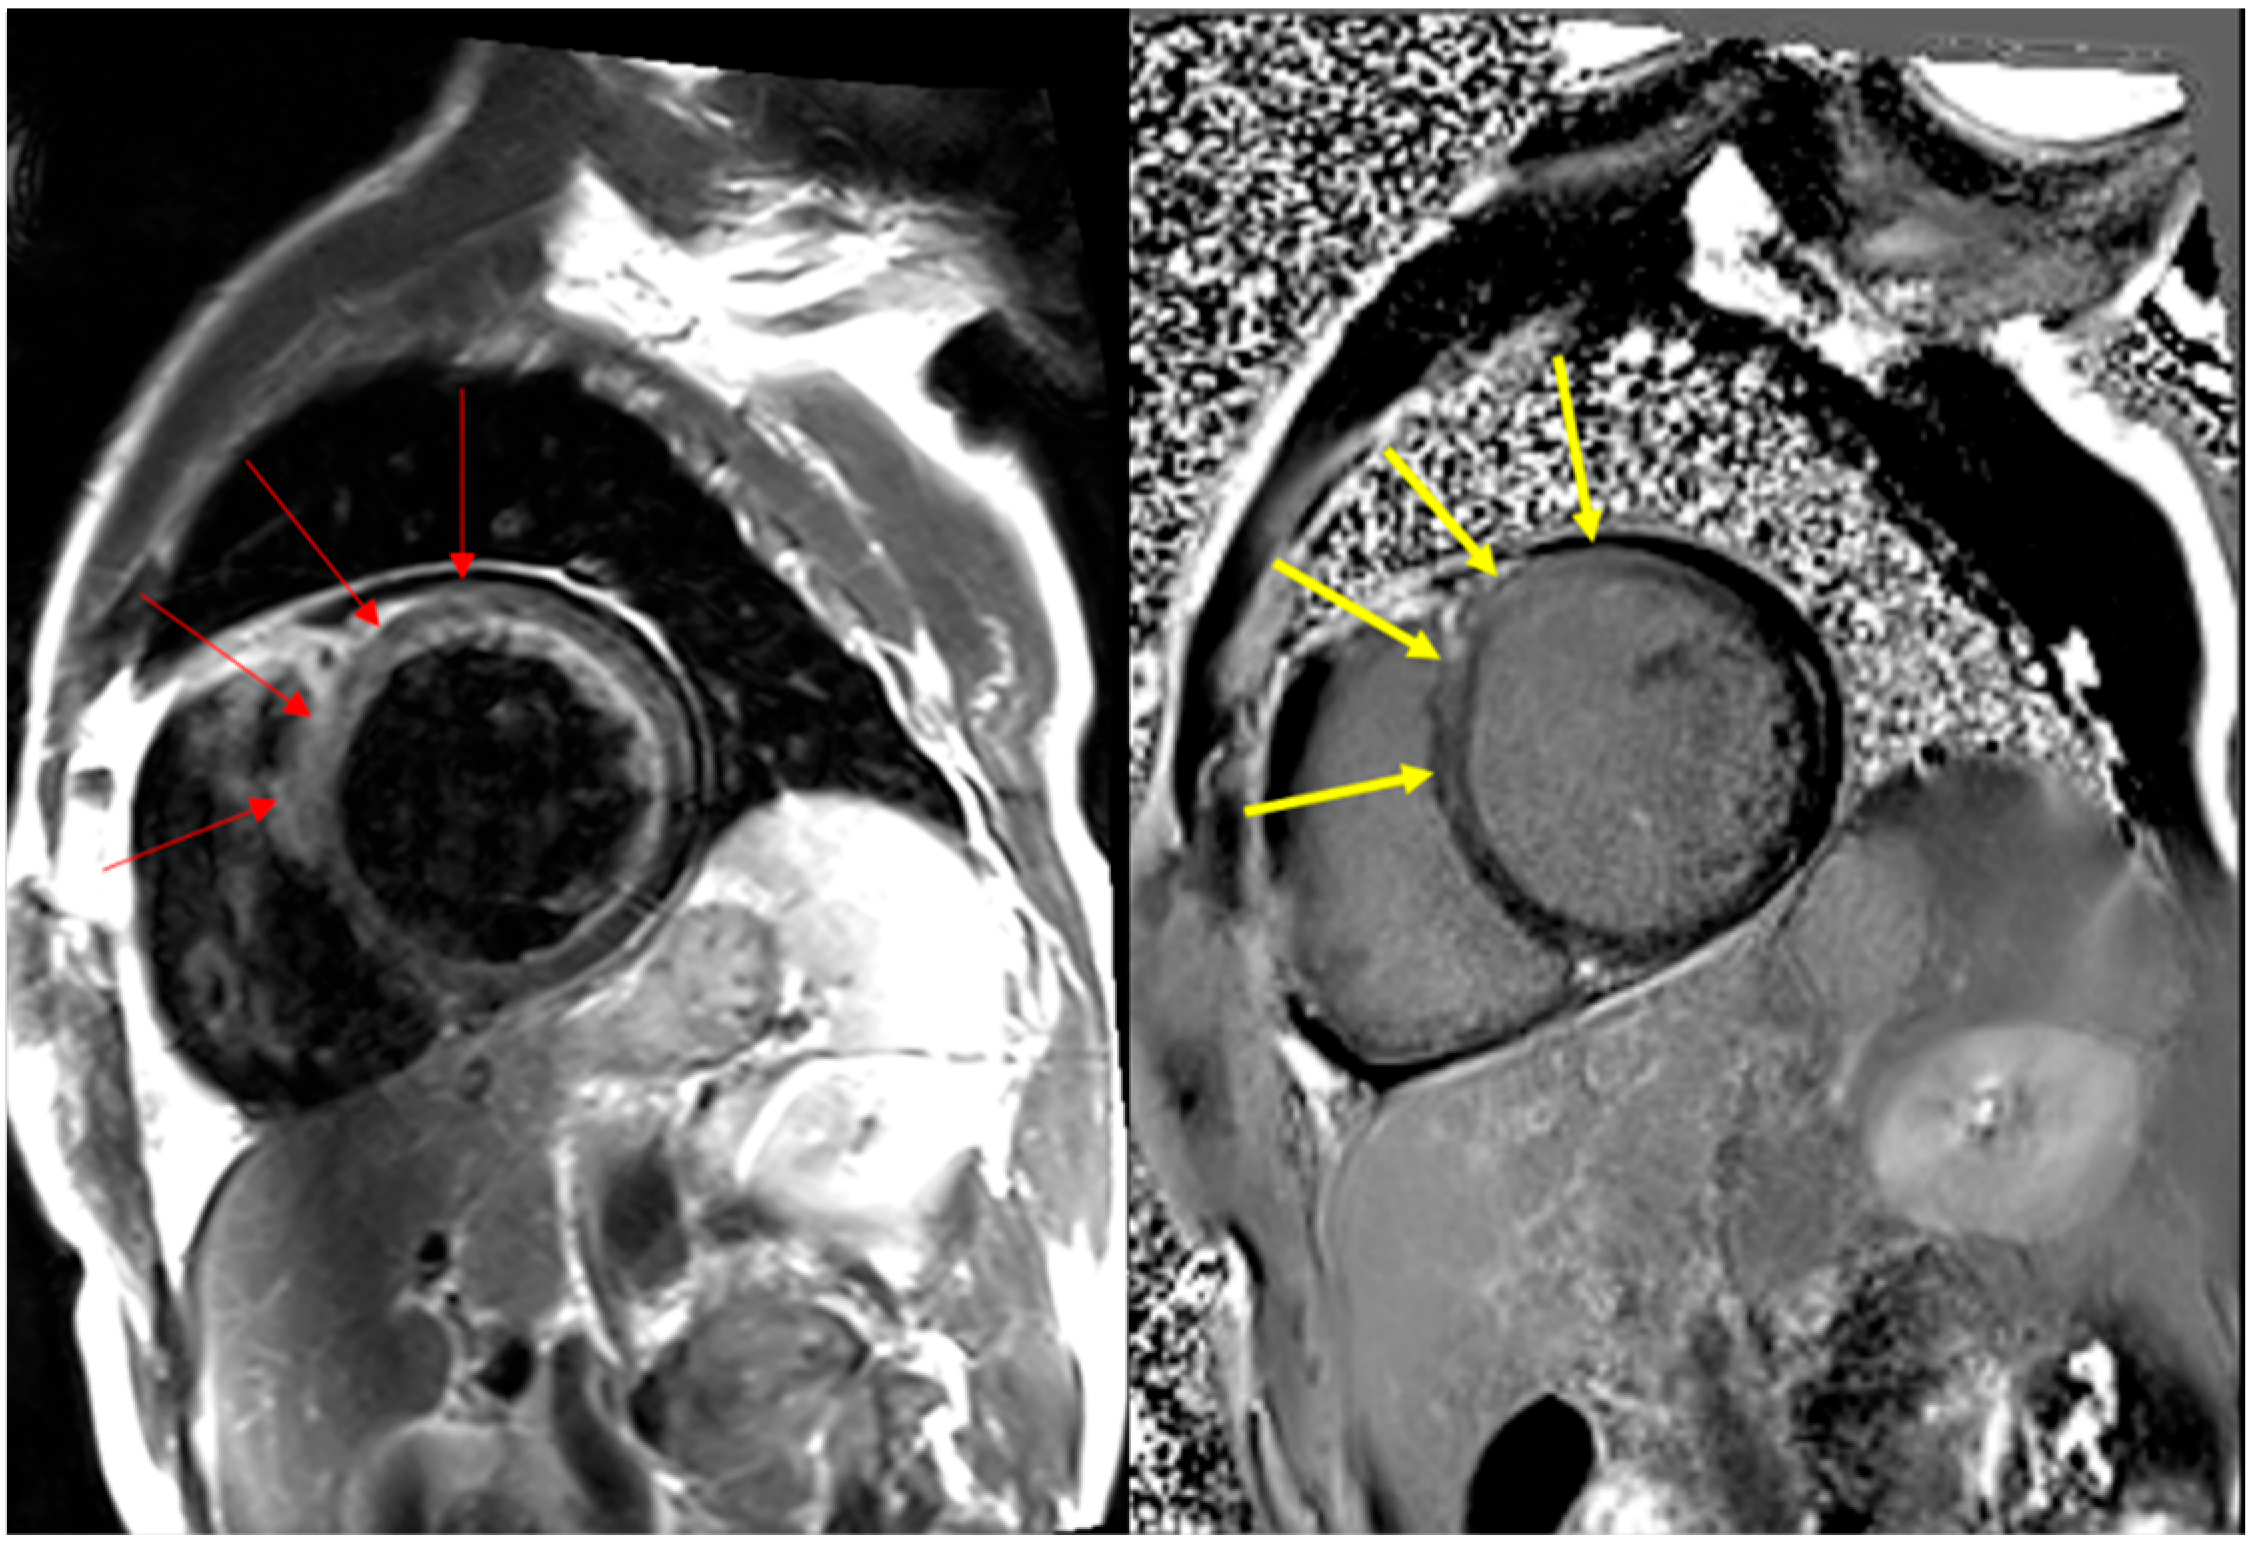

| Our case 1 | 59 | M | 24 | dyspnea, leg edema | Patchy midmyocardial LGE | 22.7 (ng/mL) | # 0.019 (ng/mL) | LM | EMB | P (1st) | 3 |

| Our case 2 | 52 | M | 35 | cardiac arrest d/t ventricular fibrillation | ND | 31.3 (ng/mL) | # 2.00 (ng/mL) | LM | EMB | P (2nd) | 19 |

| Our case 3 | 19 | M | 65 | chest pain | LGE | 11.7 (ng/mL) | # 0.085 (ng/mL) | LM | EMB | M (2nd) | 3 |

| Our case 4 | 83 | M | 35 | dyspnea, palpitation due to ventricular tachycardia | LGE | 18.7 (ng/mL) | # 0.82 (ng/mL) | LM | EMB | P (3rd) | 2 |

| Our case 5 | 69 | F | 60 | dyspnea, chest discomfort | Patchy subepicardial and midmyocardial LGE | 23.4 (ng/mL) | # 0.667 (ng/mL) | LM | EMB | M (3rd) | 2 |

| Our case 6 | 38 | M | 18 | myalgia, dyspnea | Patchy subepicardial and midmyocardial LGE and PE | 15.96 (ng/mL) | # 0.233 (ng/mL) | LM | EMB | P (3rd) | 12 |